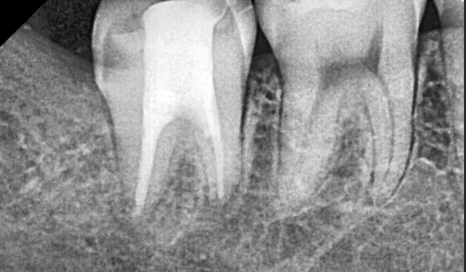

문제는 사랑니 자체보다

바로 앞어금니 상태였습니다.

엑스레이와 입안 사진을 통해 확인해 보니,

1년 반 사이에 사랑니뿐만 아니라,

앞에 치아까지 충치가 생겨있었습니다.

심지어 충치가 꽤나 많이 진행되어

이미 신경 가까이까지 진행된 상황이었습니다.

또한 양쪽 아래 사랑니 모두

엑스레이상에서 아래턱 신경관과 겹쳐 보였습니다.